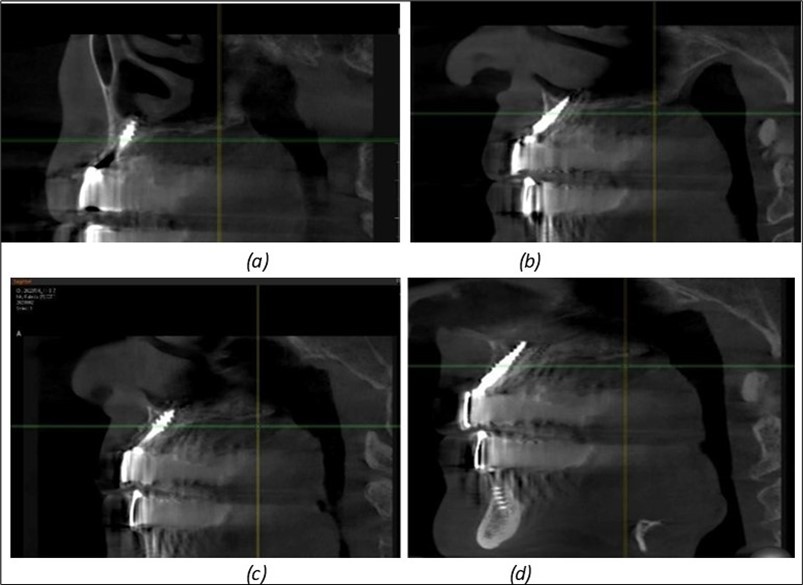

Figure 8.(a), (b) Sinus lift and grafting area with two stage implants before their removal. (c) area of fixation of BCS and TPG implants, avoiding the sinus lift and grafting area

(a), (b) Sinus lift and grafting area with two stage implants before their removal. (c) area of fixation of BCS and TPG implants, avoiding the sinus lift and grafting area